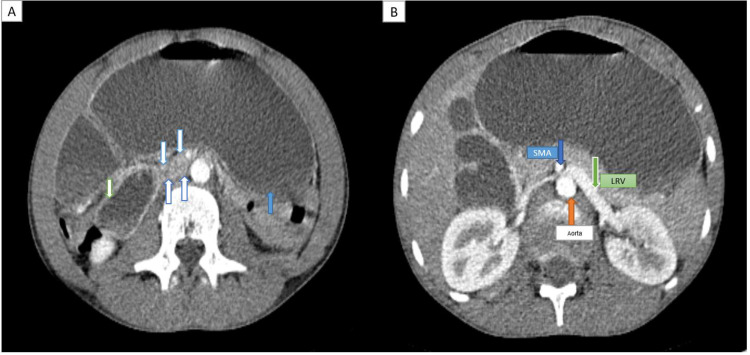

Superior mesenteric artery (SMA) syndrome, also known as Wilkie syndrome, is an uncommon condition marked by the compression of the third segment of the duodenum between the SMA and the aorta, often occurring after rapid weight loss, particularly in young, slim individuals. Symptoms consist of epigastric pain, bloating, and vomiting. Nutcracker syndrome (NCS) is characterized by the compression of the left renal vein (LRV) between the superior mesenteric artery and the aorta. This condition results in venous varices and elevated pressure within the LRV, which may manifest as hematuria, proteinuria, pelvic congestion, and flank pain. Although each of these syndromes is infrequent, their simultaneous incidence is remarkably occasional. This case report examines a young male patient diagnosed with both SMA syndrome and NCS, emphasizing the importance of considering these conditions in the differential diagnosis of abdominal and renal symptoms.